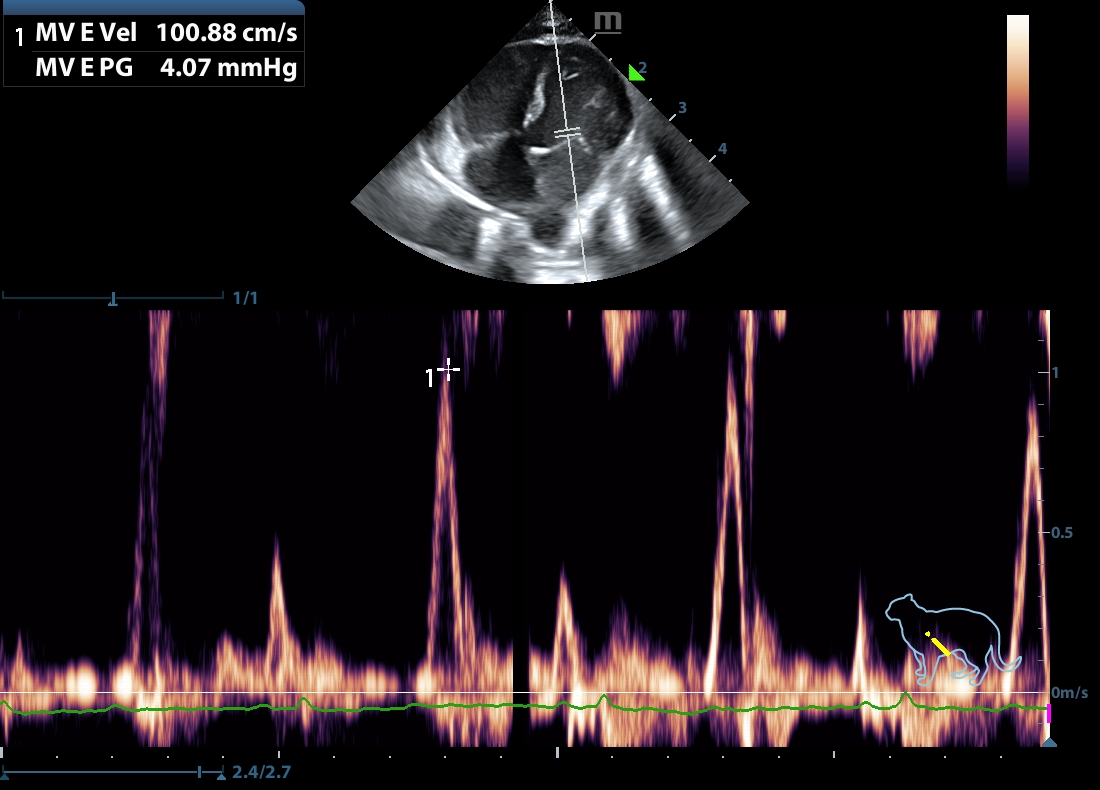

202507112257390163CARD.JPG